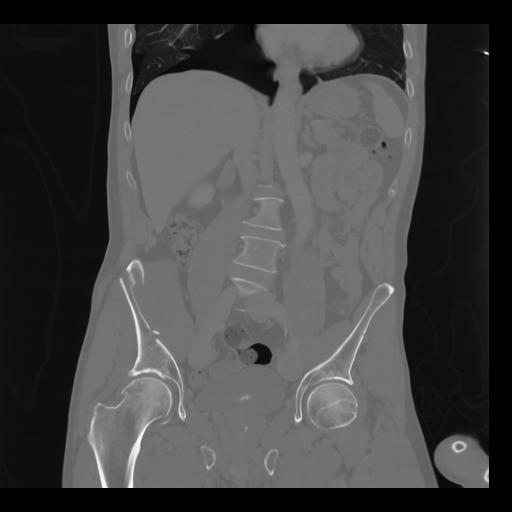

35 CUERPO,CE,Coronal,3.000,CUERPO,Coronal,